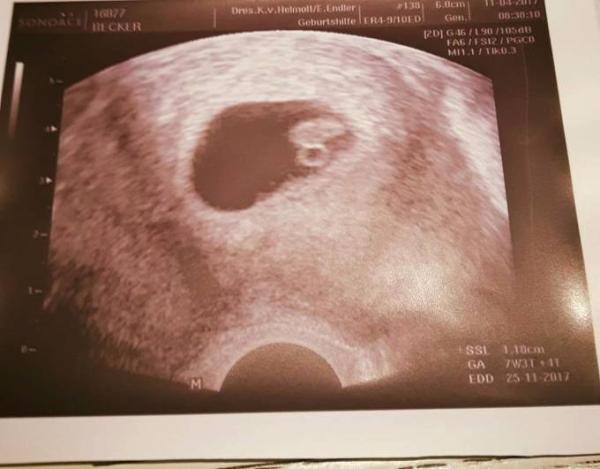

Hallo ihr Lieben, Wollte mal eure Meinung dazu haben... Bis fix und fertig. Die Dame von US sagte da wäre nichts zu sehen und man müsse eine Ausschabung machen... Bild unten und vergrößert damit man es besser sehen kann. Lieben Dank

Bild zu 1.ultraschall - Schwanger - wer noch? Rund um die Schwangerschaft

Ich weiss echt nicht mehr was ich tun soll... Eine Bekannte meint sogar, es wäre nur ein Sack in der Mitte und nicht wie ihr sagt ein Baby... bin echt am verzweifeln Aber sieht man denn wirklich nichts in der 5.ssw? Was ist dzs denn für ein Fleck wenn es kein Baby ist? Wirklich nur ein Sack?

In der 5.ssw sieht man auch noch nicht so viel. Erst in der 7. Oder 8. Woche sieht man mehr plus Herzschlag So sah meins in der 8.ssw aus

Ich war gestern in einem KH in dem schon seit längerer Zeit keine Geburten stattfinden ca. seit 8 Jahren... Erstens als ich den Termin bei denen abmachte wussten die gar nicht, dass sie Ultraschall machen Als ich dann dort war, fing die Ärztin an mit dem Gerät auf meinem Bauch rumzufuchteln... und sagte: " mhhh das sieht nicht gut aus... wenn ich wüsste, ob wir das Gerät haben um Vaginal zu schallen..." Sie sah um sich herum und fand in einer Schublade das Gerät, noch in der ORIGINAL VERPACKUNG obwohl das Ultraschallgerät seit 2005 dort installiert ist... boah ich sags euch... und dann kam dieses Bild raus das ich am Anfang postete... und sprach von einer FG, Windei, Ausschabung... Habe heute wieder zurück gerechnet und kam auf das Ergebnis dass ich erst seit 4+... Wochen Schwanger bin. Periode war: 7.04 und ES war: ab den 22.04